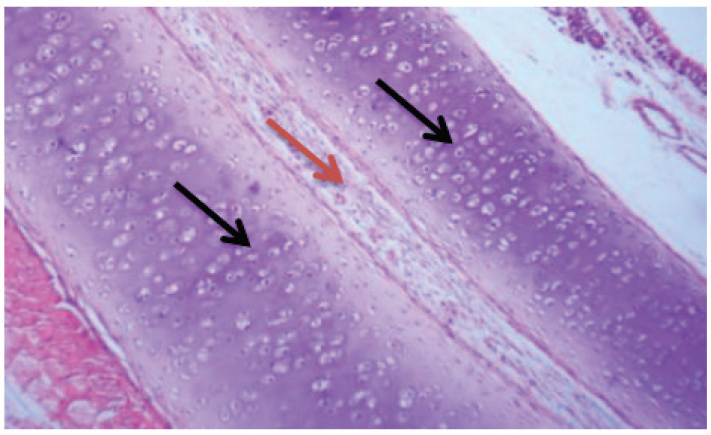

Fig. 4. The trachea (control group ) show (black arrow tracheal cartilage) and (red arrow connective tissue).

Fig. 6. Group of infected rabbits lung (A) Bronchiols show emphysema aggregation of lymphocytic cell (black arrow)( B) show emphysema structure atelectasis (black arrow) H&E stain 400X and lung H&E stain 200X. Gross examination of sacrificed animals (group of infected rabbits) showed hemorrhage in the upper respiratory tract (Fig. 3). The trachea exhibited a semi-circular hyaline cartilage structure (Fig. 4), and the bronchi branched into left and right bronchioles, consistent with typical mammalian respiratory anatomy. Normal histological details of trachea of control group• Tunica mucosa • Tunica submucosa • Tunica adventitia • C-shaped hyaline cartilage (Fig. 5A) • score lesion of Pathological Changes • Emphysema was observed in 3 out of 5 cases (60%) (Fig. 4). • No pathological changes were seen in 2 cases (40%). • Vascular changes, including congestion, thrombosis, and alveolar hemorrhage, were noted in 10% of affected cases. Comparative morphologyLight microscopy analysis confirmed Gram-negative rods for Raoultella planticola. However, differentiation from Klebsiella spp. was challenging due to morphological similarities (Fig. 2A and B). The histological findings of emphysema and atelectasis align with Blagojević et al. (2018), who described similar structural changes in respiratory infections. The observed hemorrhage and vascular congestion support Castro et al. (2001), who linked these changes to bacterial-induced trauma. The 60% incidence of emphysema suggests that Raoultella planticola primarily induces chronic obstructive pulmonary disease (COPD)-like lesions, differing from Sarhad (2011), who reported fibrinous pleuropneumonia as the dominant pathology. This discrepancy may stem from differences in infection routes or host susceptibility. The short respiratory passage and direct bronchial branching in rabbits (Abdelsalam and Al Sadrani, 2015) likely contribute to higher lung infection rates. Additionally, the similarity between Raoultella and Klebsiella (Alampoondi Venkataramanan et al., 2021) complicates microscopic differentiation, necessitating advanced diagnostic methods like Vitek2.Contrary to Vinshia, J. J., (2024), this study found no fibrinous bronchopneumonia, instead emphasizing edema and congestion (Das and Bhagman, 1997). The reclassification of Raoultella from Klebsiella prior to 2001 further underscores the need for precise microbiological identification (Fig. 8). This study highlights Raoultella planticola's potential to cause respiratory pathology, warranting further investigation into its zoonotic risks.